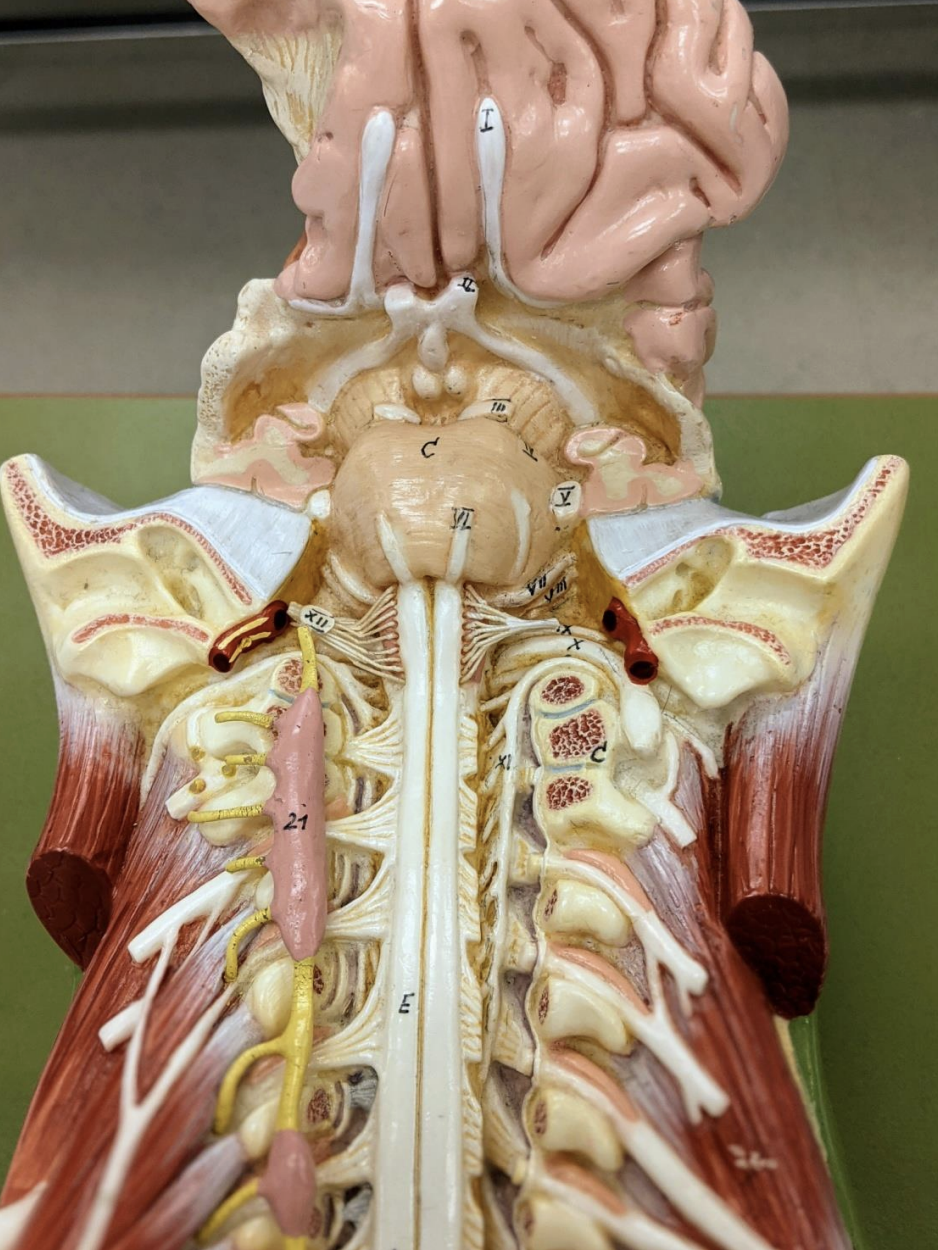

Cranial Nerves